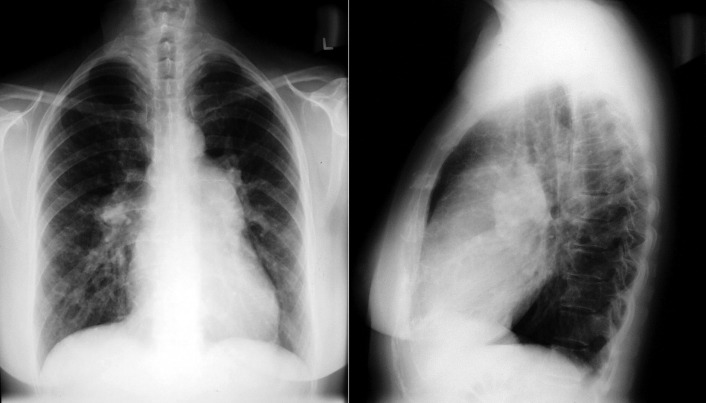

See Figures 18-5 to 18-31 . Possible findings are discussed in the following sections.